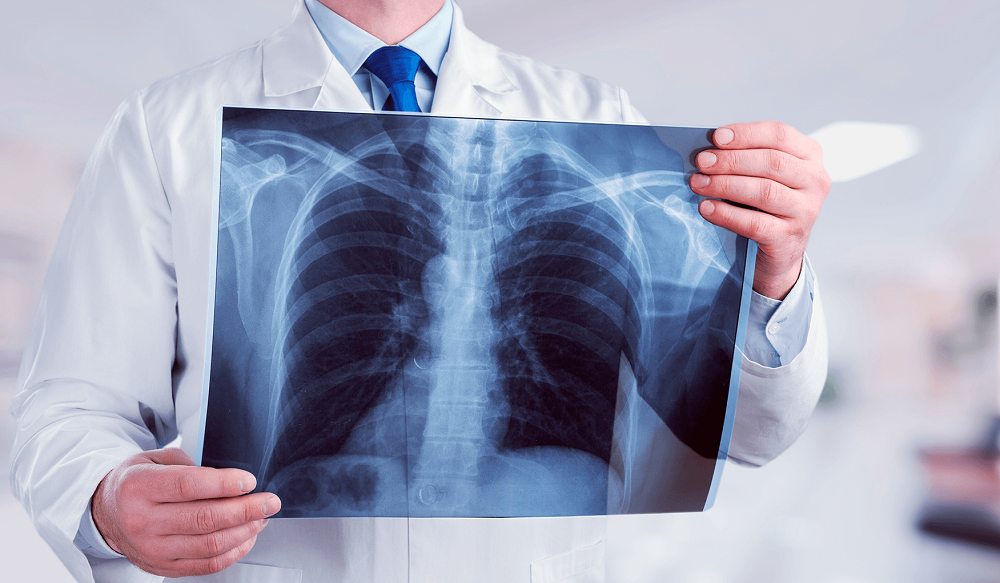

Ранок у поліклініці, черга біля рентген-кабінету, хтось тримає в руках телефон з електронним направленням, а хтось нервово питає реєстратуру: «А без папірця від лікаря взагалі пускають?» Такі сцени повторюються щодня по всій країні, бо флюорографія давно перестала бути просто «знімком легень раз на рік» — вона вплелася в систему медичних гарантій, електронної охорони здоров’я та щоденних турбот про власне дихання.

Програма медичних гарантій, яку адмініструє Національна служба здоров’я України, чітко визначає: флюорографія входить до пакету профілактики, діагностики та лікування захворювань органів дихання. Безоплатно її проводять виключно за електронним або паперовим направленням від лікаря. Саме він оцінює клінічну потребу — чи то скарги на задишку, чи тривалий кашель, чи контакт з хворим на туберкульоз, чи підготовка до операції.

Сучасна цифрова флюорографія дає дозу опромінення приблизно 0,02–0,05 мЗв — це менше, ніж один рентген зуба чи кілька перельотів літаком. Проте лікарі не роздають направлення «на всяк випадок», бо надмірна діагностика призводить до зайвого опромінення, особливо для молодих людей та вагітних.

Флюорографія залишається одним з найпростіших і найдоступніших способів «підглянути» за легенями. Вона не замінить КТ чи МРТ при серйозній патології, але часто стає першим тривожним дзвіночком, що рятує життя. А питання про направлення — це просто ключ до безоплатного доступу в системі, яку держава намагається зробити зручною, хоч і не завжди встигає за реальними потребами людей.